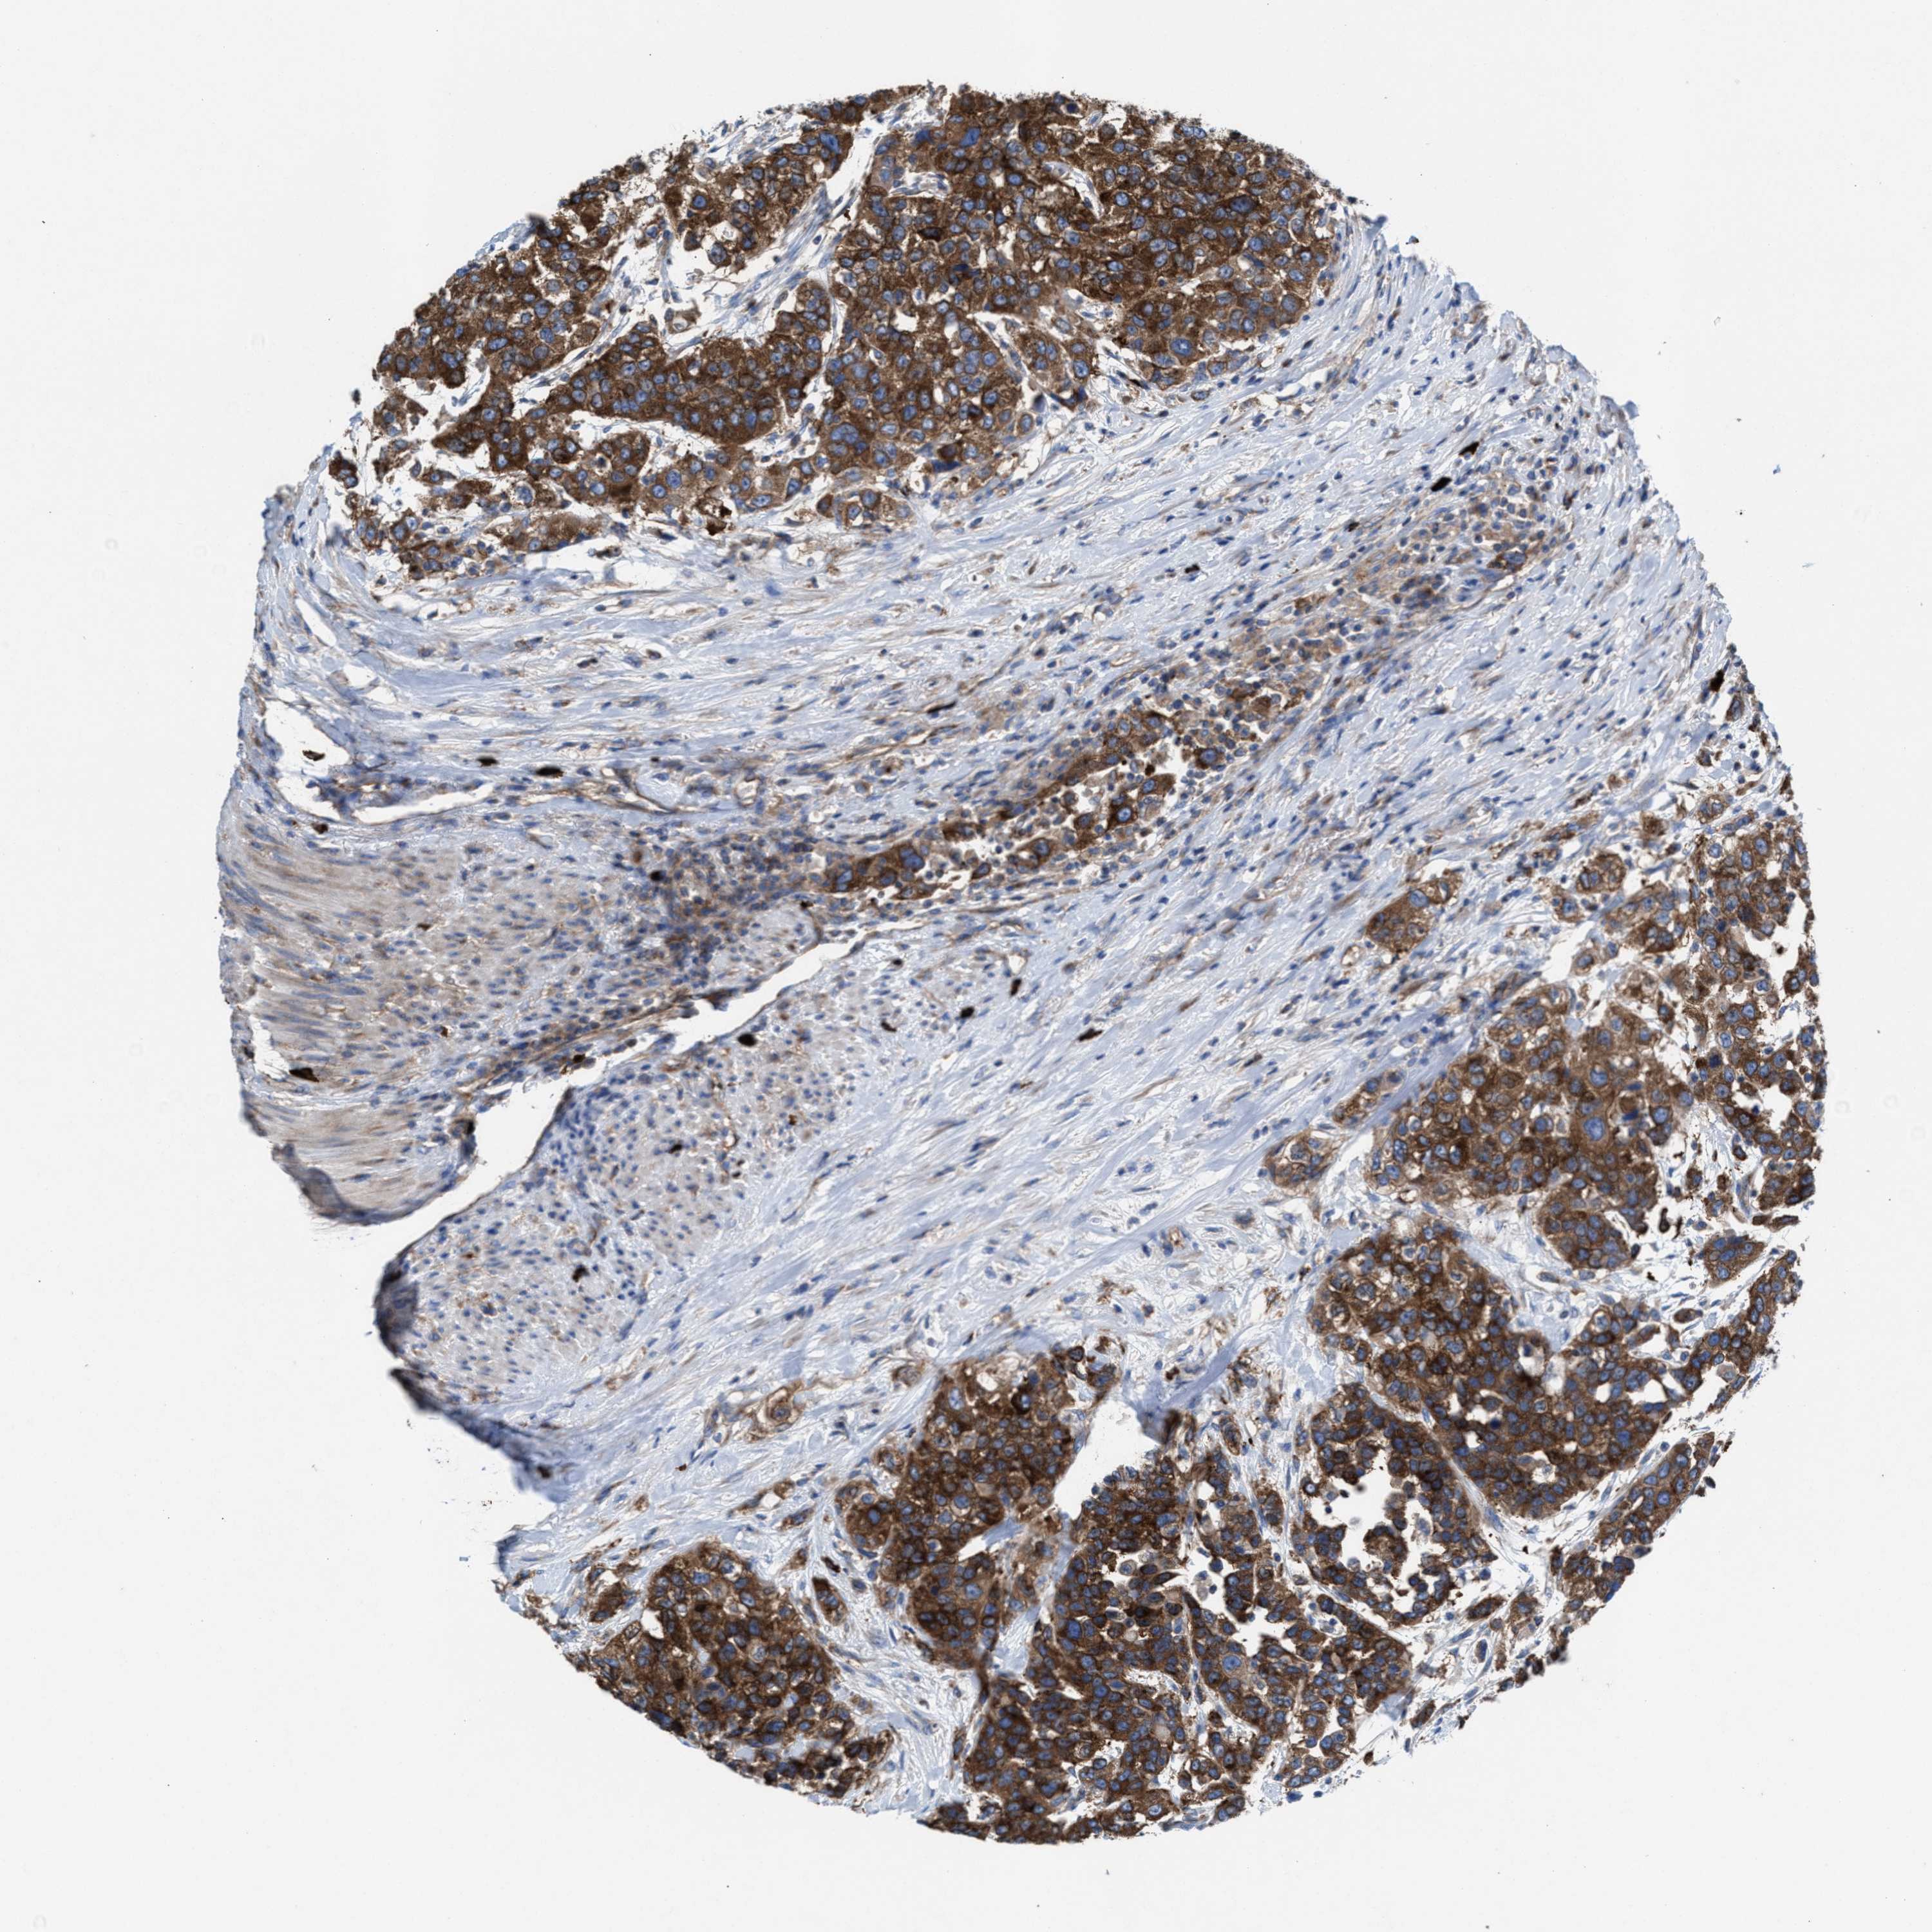

UROTHELIAL CANCER - Protein expressioni

A mouse-over function shows sample information and annotation data. Click on an image to view it in a full screen mode. Samples can be filtered based on level of antibody staining by selecting one or several of the following categories: high, medium, low and not detected. The assay and annotation is described here.

Note that samples used for immunohistochemistry by the Human Protein Atlas do not correspond to samples in the TCGA dataset.

Antibody stainingi

Antibody staining in the annotated cell types in the current human tissue is reported as not detected, low, medium, or high, based on conventional immunohistochemistry profiling in selected tissues. This score is based on the combination of the staining intensity and fraction of stained cells.

Each image is clickable and will lead to virtual microscopy that enables deeper exploration of all samples and also displays staining intensity scores, fraction scores and subcellular localization as well as patient and tissue information for each sample.

Antibody HPA022251

Staining

High

Medium

Low

Not detected

Intensity

Strong

Moderate

Weak

Negative

Quantity

>75%

75%-25%

<25%

None

Location

Nuclear

Cytoplasmic/membranous

Cytoplasmic/membranous,nuclear

Urothelial carcinoma, Low grade

Urothelial carcinoma, High grade